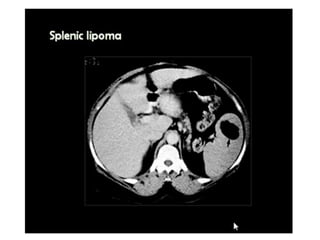

This document discusses the spleen and causes of splenomegaly (enlarged spleen). It begins by thanking radiologists for their assistance. Simple cyst criteria are outlined. Splenogonadal fusion and sarcoidosis are mentioned. The main causes of splenomegaly are then listed, including infections, portal hypertension, hemolytic anemias, hematological malignancies, infiltrative disorders, collagen vascular disorders, and congestive cardiac failure.